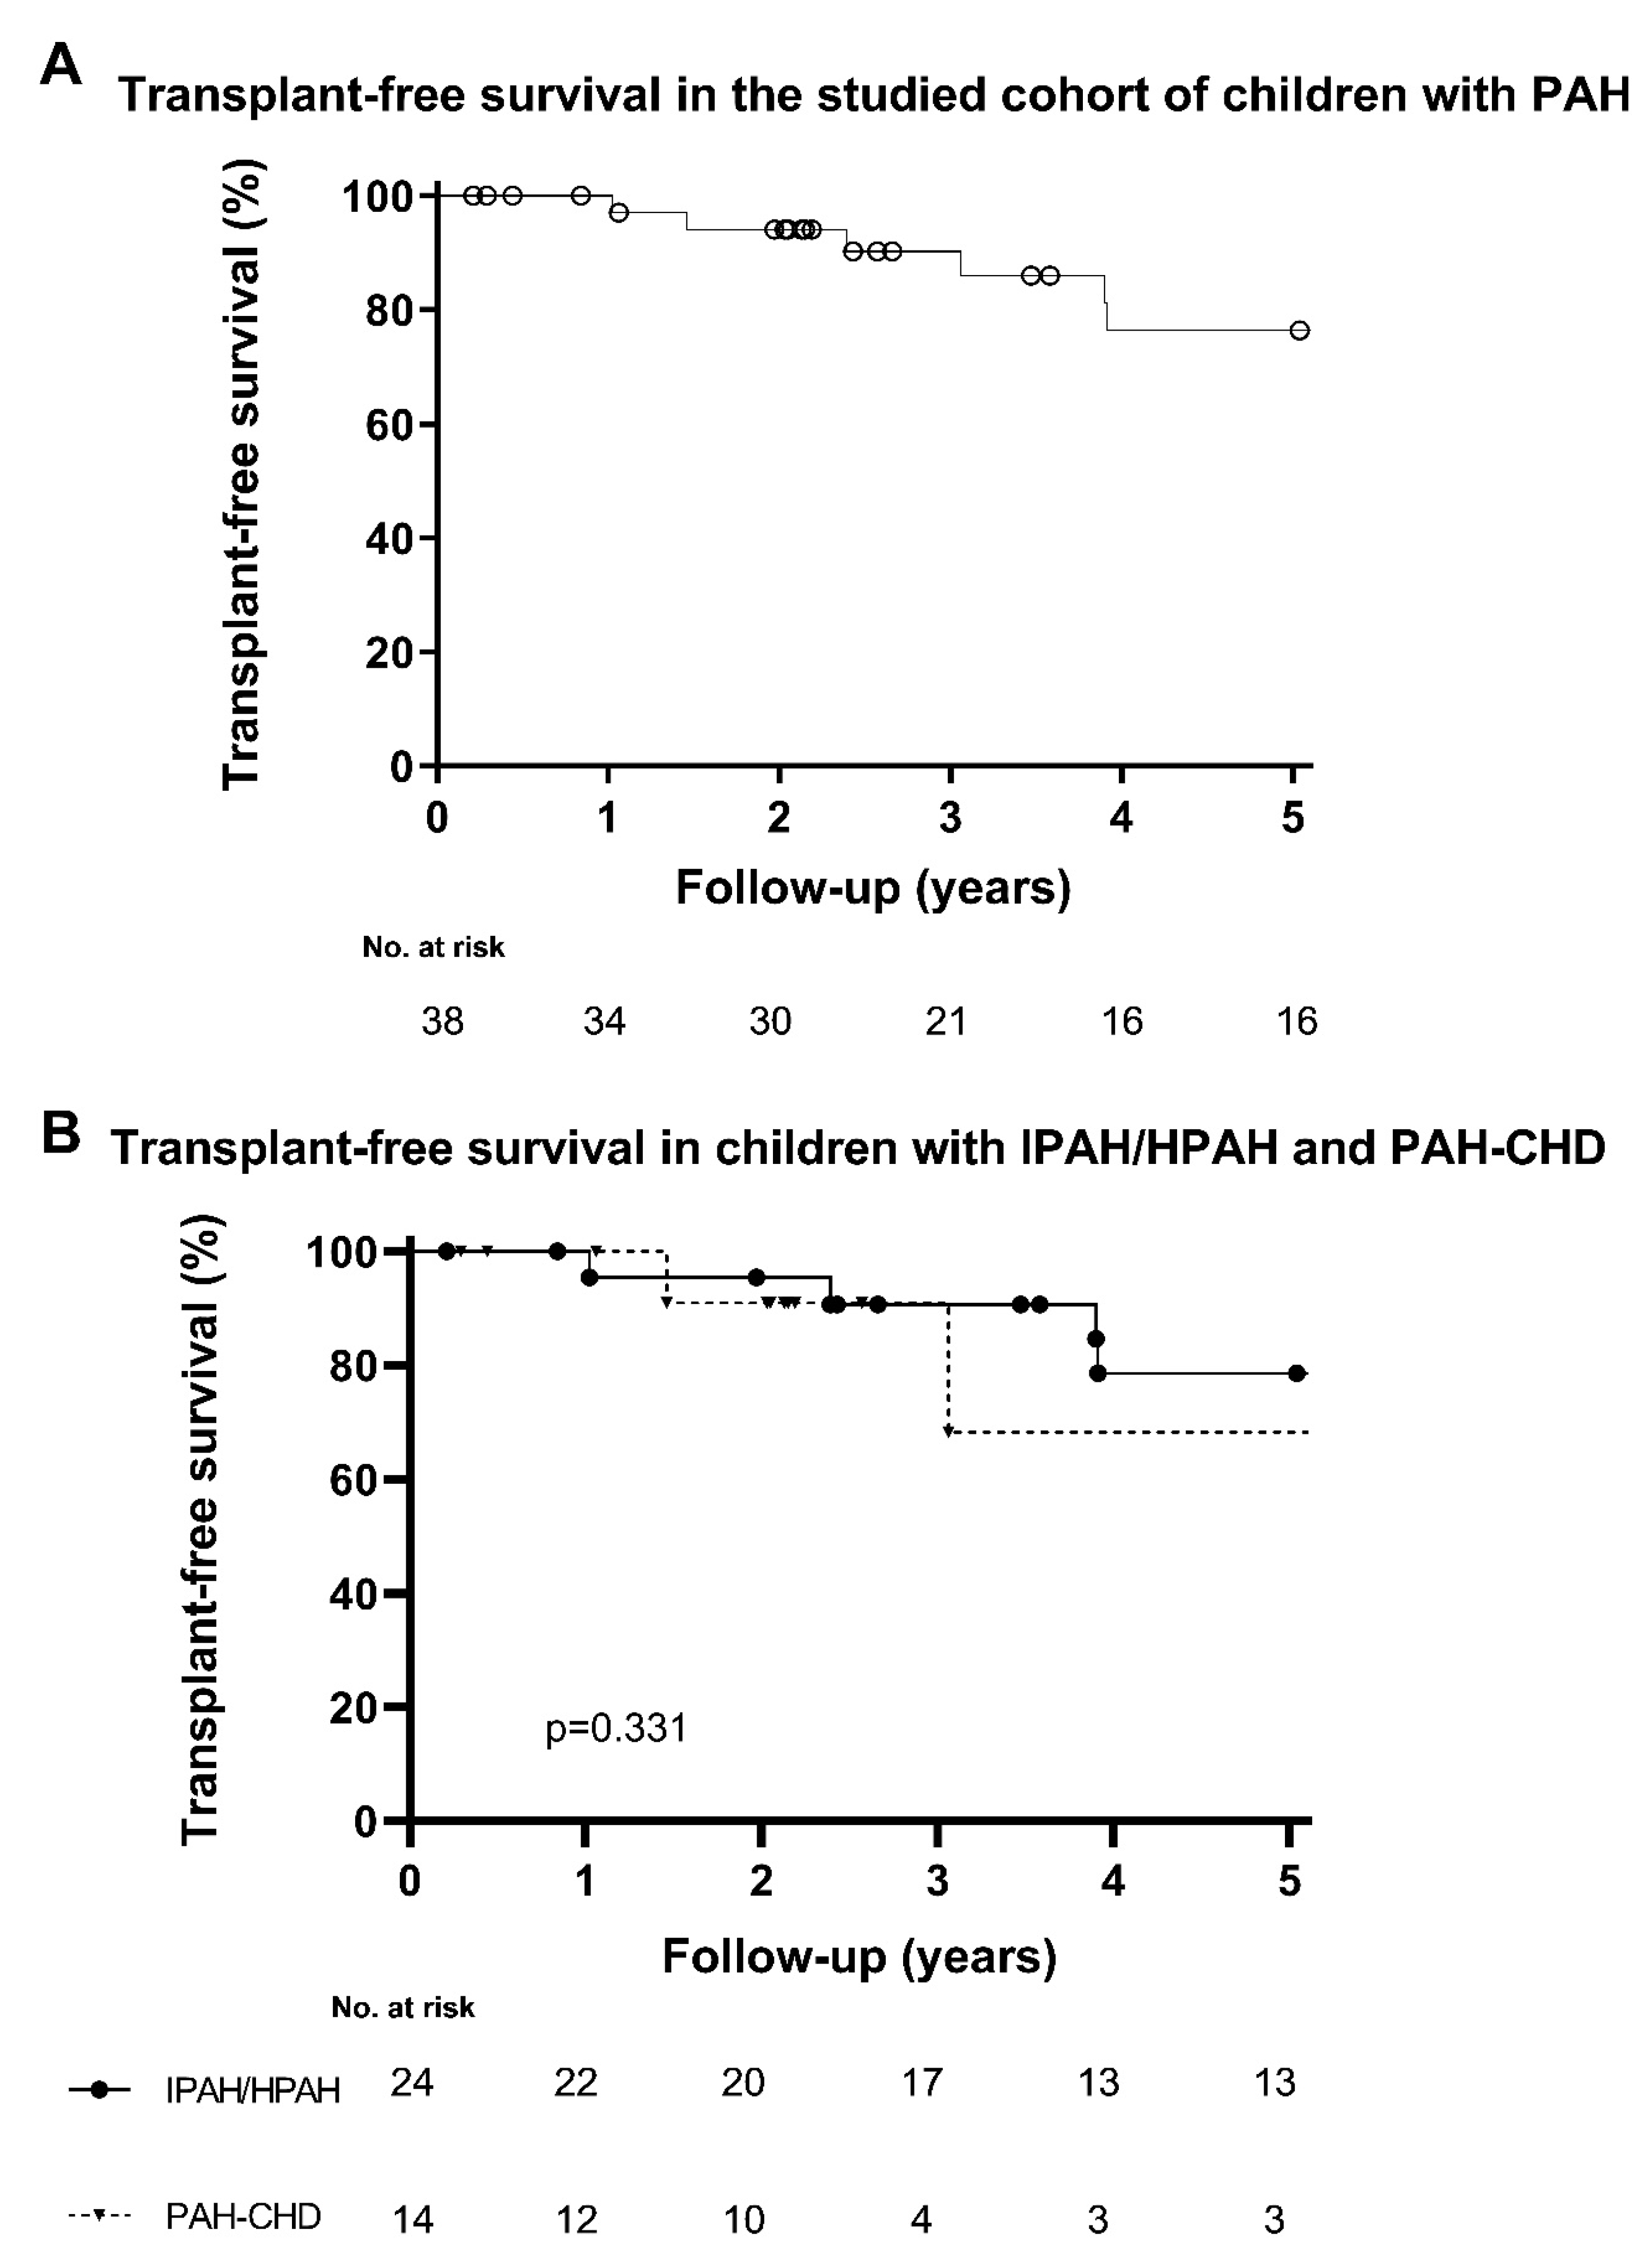

3. Results

4. Discussion

5. Conclusions